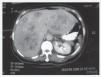

Resumen clínico. Femenino de 51 años de edad, con dolor abdominal de 3 años de evolución en cuadrante superior derecho, náusea, vómito, diarrea, diaforesis, palpitaciones y enrojecimiento facial. La tomografía axial (Figuras 1 y 2), mostró múltiples masas en ambos lóbulos del hígado; los niveles urinarios de ácido 5-hidroxiindolacético fueron normales. Se diagnosticó TCMH basado en octreótide marcado con Indio 111 (Figura 3), laparotomía exploradora sin encontrarse lesión primaria y la biopsia hepática, con tinción de grimelius y cromogranina A positiva para tumor carcinoide (Figura 4). La paciente recibió octreotide LAR controlándose los síntomas de síndrome carcinoide, y posteriormente fue sometida a hemipatectomía izquierda. Actualmente, se encuentra en control de su sintomatología con octreótide LAR y en lista de espera de trasplante hepático de donador cadavérico.

Figura 1. TAC contrastada con múltiples lesiones hipodensas.